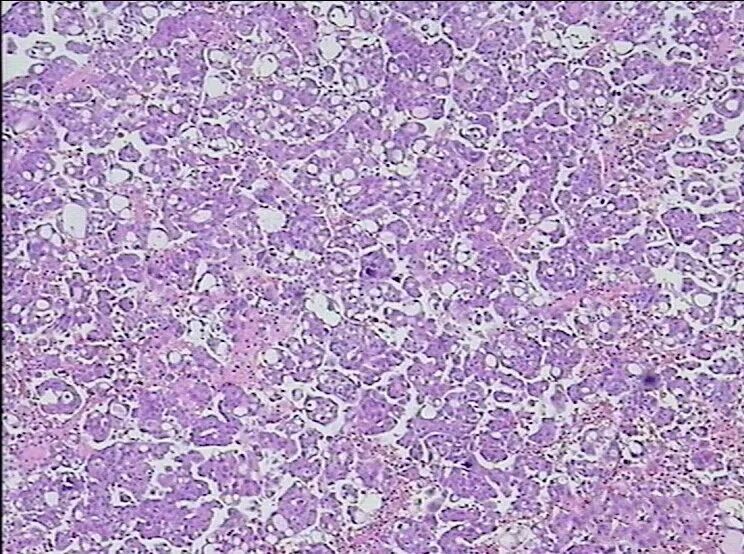

为了进一步鉴别诊断,在与临床大夫和患者沟通后,将胸水标本的细胞渣包埋制作成细胞蜡块,行石蜡包埋切片,并做免疫组化检查。免疫组化结果显示:EMA(+);D2-40(-);CA125(+)ER(+,弱,60%);P16(+);P53(-);Her-2(±);Ki-67(+,f30%)。结果表明腹水细胞蜡块镜下可见腺癌细胞,形态学及免疫组化支持浆液性乳头状癌

图5患者细胞蜡块HE染色镜下所见